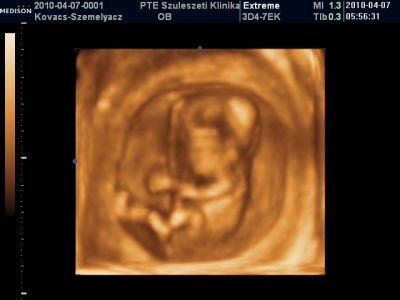

Mares, gyönyörűséges a kisbabád, nagyon boldog lehetsz